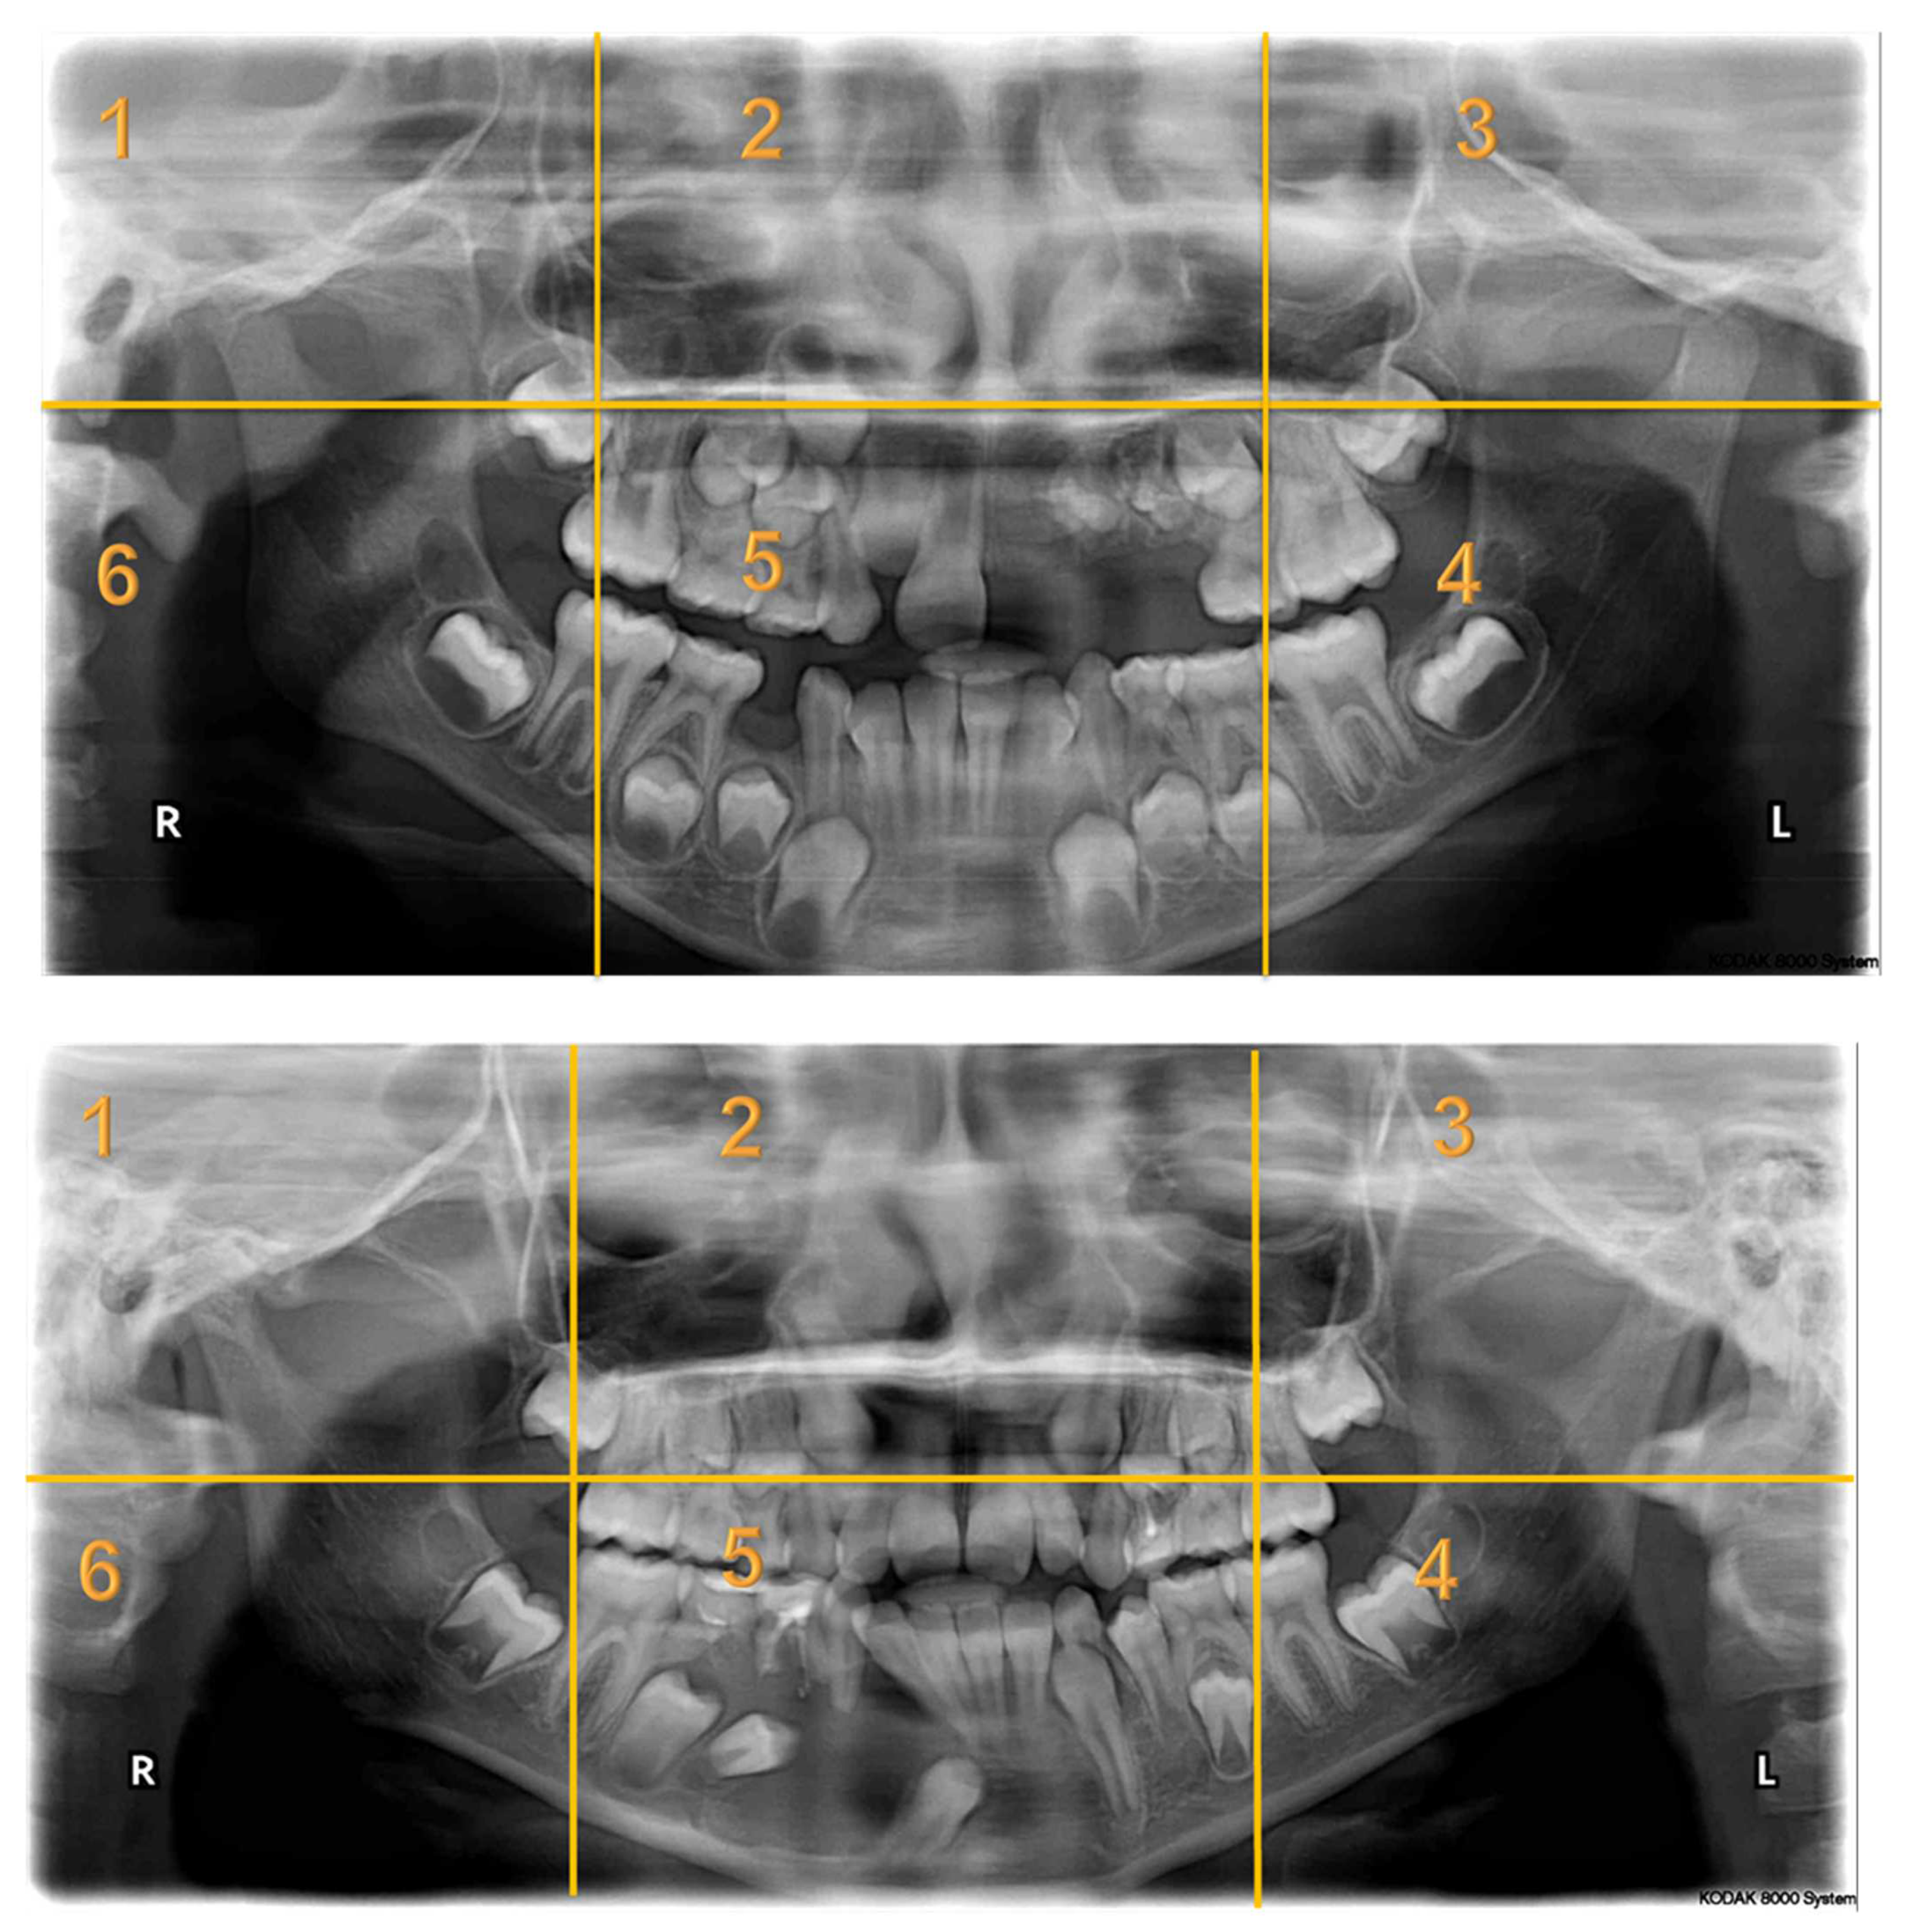

Appendix A. Radiographs Included in the Study

| Radiographs with Abnormalities | Number of Sextants Involved | Number of AOI a | Number of Participants | Total Recorded Observation b |

|---|---|---|---|---|

| Radiograph 1 | Multiple | 3 | 30 | 90 |

| Radiograph 2 | Multiple | 8 | 30 | 240 |

| Radiograph 3 | Single | 2 | 30 | 60 |

| Radiograph 4 | Single | 2 | 30 | 60 |

| Radiograph 5 | Single | 1 | 30 | 30 |

| Radiograph 6 | Single | 1 | 30 | 30 |

| Radiograph 7 | Single | 1 | 30 | 30 |

| Overall Observations | 540 |